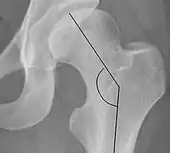

Crowe classification

In 1979 Dr. John F. Crowe et al. proposed a classification to define the degree of malformation and dislocation. Grouped from least severe Crowe I dysplasia to most severe Crowe IV.[13] This classification is very useful for studying treatment results.

Rather than using the Wiberg angle because it makes it difficult to quantify the degree of dislocation they used 3 key elements to determine the degree of subluxation: A reference line at the lower rim of the "teardrop", junction between the femoral head and neck of the respective joint and the height of the pelvis (vertical measurement). They studied anteroposterior pelvic x-rays and drew horizontal lines through the lower rim of a feature called "teardrop". The distance between this line and the middle lines of the junction between femur head and neck gave them a measure of the degree of femur head subluxation. They further established that a "normal" diameter of the femur head measures 20% of the height of the pelvis. If the middle line of the neck-head junction was more than 10% of the pelvis height above the reference line they considered the joint to be more than 50% dislocated.[13]

The following types resulted:[13]

ClassDescriptionDislocation

Crowe IFemur and acetabulum show minimal abnormal development.Less than 50% dislocation

Crowe IIThe acetabulum shows abnormal development.50% to 75% dislocation

Crowe IIIThe acetabula is developed without a roof. A false acetabulum develops opposite the dislocated femur head position. The joint is fully dislocated.75% to 100% dislocation

Crowe IVThe acetabulum is insufficiently developed. Since the femur is positioned high up on the pelvis this class is also known as "high hip dislocation".100% dislocation